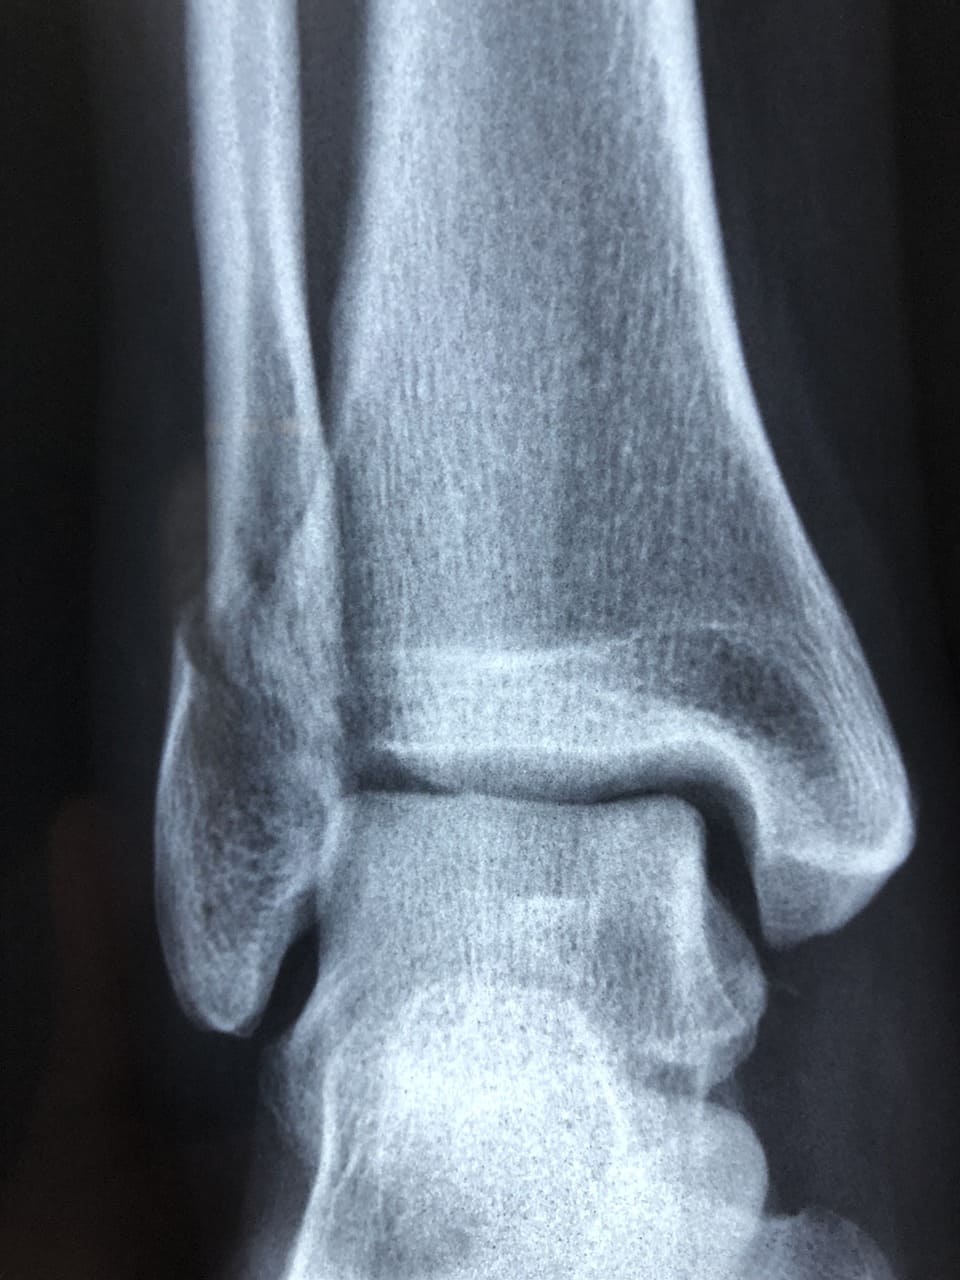

스트레스성 골절은 뼈에 반복적인 충격이 가해지면서 미세한 금이 가는 상태입니다. 갑자기 운동량을 늘리거나 딱딱한 바닥에서 오래 걸을 때 발생할 수 있습니다. 처음에는 운동할 때만 통증이 느껴지다가 점점 일상생활에서도 아프게 됩니다. X선 검사에서 잘 보이지 않는 경우도 있어서 MRI 검사가 필요할 수 있습니다.